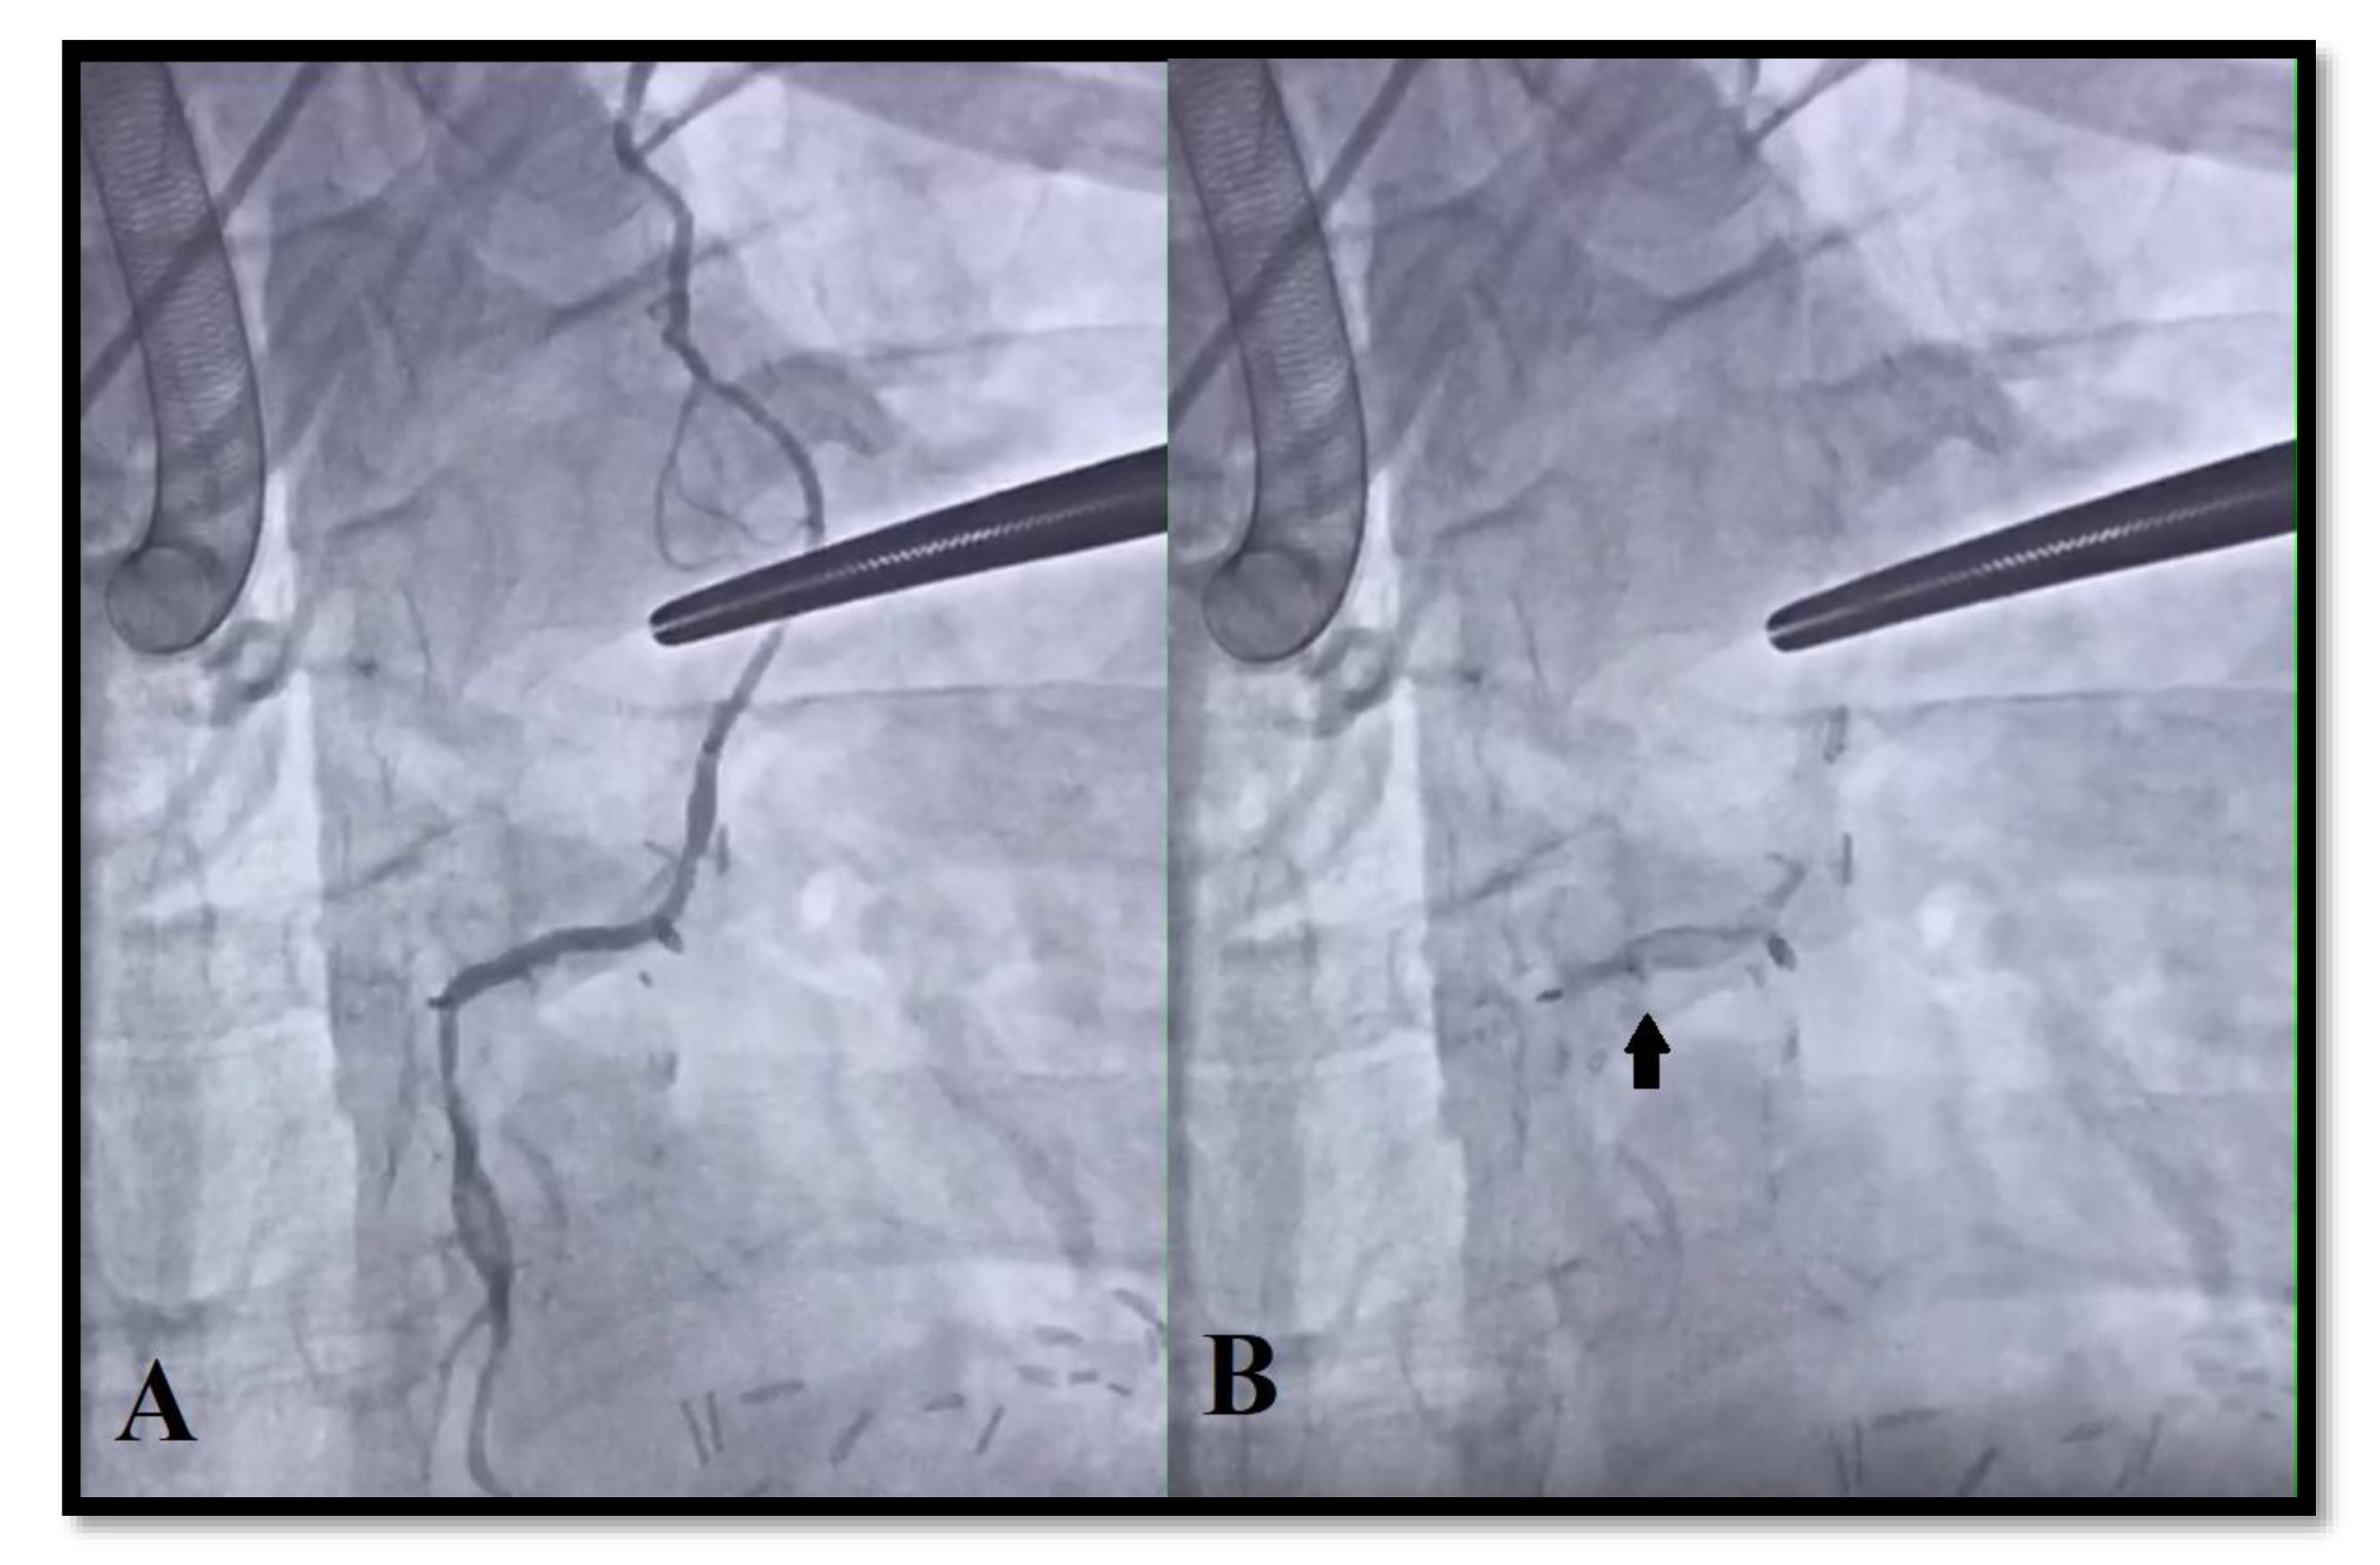

2.4. Intraoperative Angiography